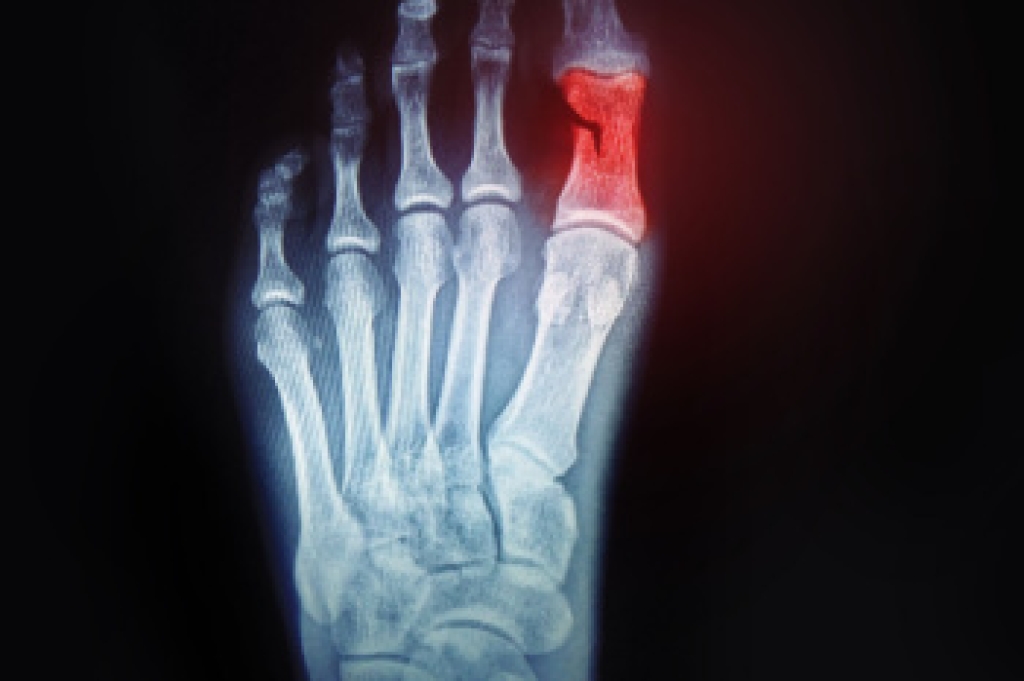

Diagnosis of cuboid syndrome is often difficult, and it is often misdiagnosed. X-rays, MRIs and CT scans often fail to properly show the cuboid subluxation. Although there isn’t a specific test used to diagnose cuboid syndrome, your podiatrist will usually check if pain is felt while pressing firmly on the cuboid bone of your foot.